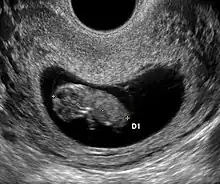

Embryon à 5 semaines

Embryon à 5 semaines. L'embryon est entre les deux croix. La structure arrondie au-dessus de l'embryon est la vésicule vitelline

L'embryon est visible dès 5 semaines en cas d'utilisation de sonde endovaginale de haute fréquence. Il se présente comme une zone hyperéchogène coincée entre la vésicule vitelline et la paroi du sac ovulaire. Une activité cardiaque peut être visualisée. Il est déconseillé, à ce stade, d'utiliser le doppler pour entendre l'activité cardiaque embryonnaire en raison d'effet délétère possible sur la formation du cœur. En raison de la sensibilité humaine au mouvement, il est parfois possible de visualiser une activité cardiaque avant la visualisation de l'embryon. En pratique, l'activité cardiaque doit être systématiquement vue dès que l'embryon mesure mm.